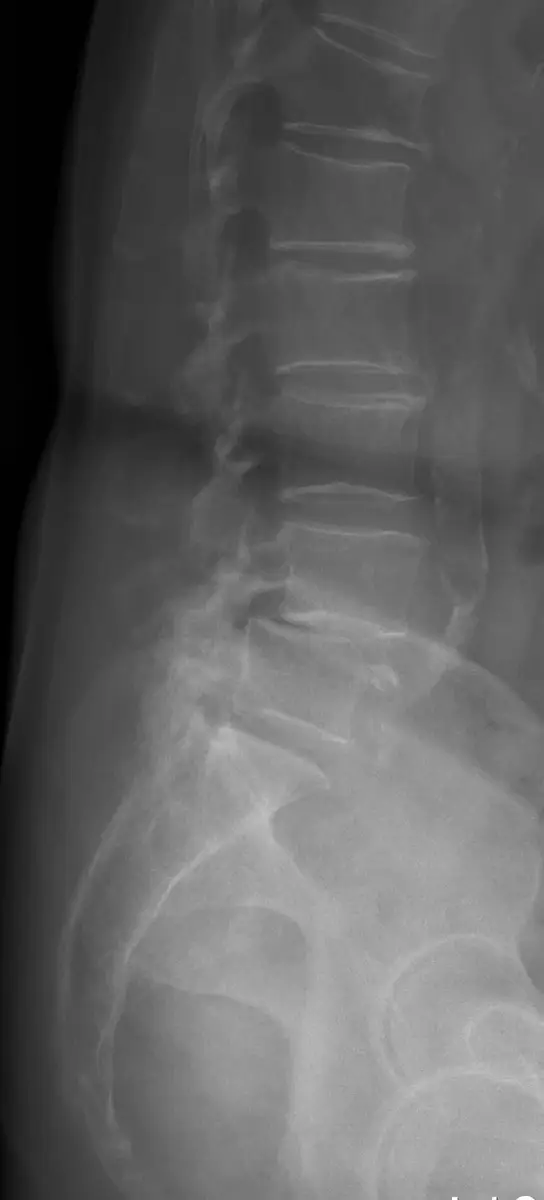

本題圖片為腰椎側位 X 光影像(lateral lumbar spine X-ray)。影像中可見以下重要發現:

- 椎骨前移(前滑脫):在腰椎下段(L4-L5 或 L5-S1 節段),可清楚見到上方椎骨相對於下方椎骨明顯向前位移,正常脊椎後緣連線(posterior vertebral line)被中斷,形成「階梯狀」排列。

- 後方結構異常:後方椎弓結構顯示有骨質缺損或不連續,與**峽部裂(spondylolysis)**相符,提示此為峽部裂型(isthmic type)脊椎滑脫。

- 椎間盤間隙:滑脫節段的椎間盤間隙有縮窄跡象。

- 腰薦椎曲度:整體腰椎前凸(lumbar lordosis)有代償性增加。

影像診斷結論:此影像符合腰椎脊椎滑脫症(lumbar spondylolisthesis),最應避免的動作為腰椎後伸(extension)。